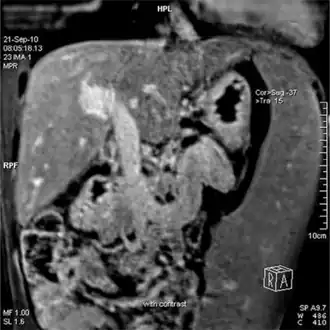

-

Magnetic resonance imaging of portal hypertension -

Portal hypertension due to cirrhosis resulting in revascularization of the umbilical vein

Ultrasonography (US) is the first-line imaging technique for the diagnosis and follow-up of portal hypertension because it is non-invasive, low-cost and can be performed on-site.[12]

A dilated portal vein (diameter of greater than 13 or 15 mm) is a sign of portal hypertension, with a sensitivity estimated at 12.5% or 40%.[13] On Doppler ultrasonography, a slow velocity of <16 cm/s in addition to dilatation in the main portal vein are diagnostic of portal hypertension.[14] Other signs of portal hypertension on ultrasound include a portal flow mean velocity of less than 12 cm/s, porto–systemic collateral veins (patent paraumbilical vein, spleno–renal collaterals and dilated left and short gastric veins), splenomegaly and signs of cirrhosis (including nodularity of the liver surface).[12]

The hepatic venous pressure gradient (HVPG) measurement has been accepted as the gold standard for assessing the severity of portal hypertension. Portal hypertension is defined as HVPG greater than or equal to 5 mm Hg and is considered to be clinically significant when HVPG exceeds 10 to 12 mm Hg.[15]